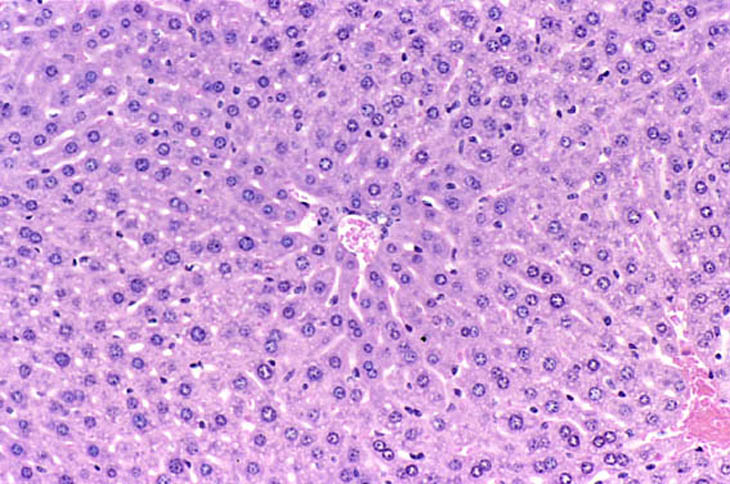

Immersion fixed liver following an overnight fast. Fixative was 10% NBF.